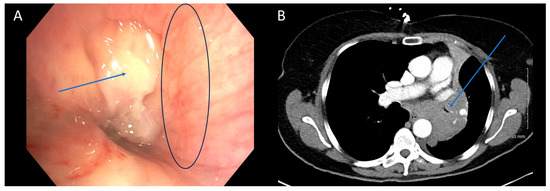

There was moderate agreement between bronchoscopy and CT in quantifying the degree of obstruction (65% agreement, Quadratic κ = 0.657, p < 0.001). Typically, when there was disagreement, it was between mild and moderate obstruction or moderate and severe obstruction. Few patients were categorized as having severe obstruction on CT (2/23, 9%) when mild obstruction was present on bronchoscopy, or mild obstruction on CT (1/61, 2%) when severe obstruction was present on bronchoscopy (Figure 1). In cases of moderate obstruction, CT tended to equally overestimate (7/19) and underestimate (7/19) the degree of obstruction. Several factors contribute to the discrepancy in the degree of obstruction between the two modalities. Bronchoscopists typically estimate the degree of obstruction visually, a subjective and variable method lacking standardization. The use of a fisheye lens in bronchoscopy may lead to an overestimation of obstruction severity, especially with variations in distance [20]. Jet ventilation, which may be used during rigid bronchoscopy lacks the ability to create significant positive end-expiratory pressure which could hold airways open more than positive pressure ventilation. This could result in a smaller airway caliber due to bulging of the posterior membrane. Additionally, the timing of the respiratory cycle during which the CT image is captured plays a role. Non-contrast CT scans are obtained during maximal inhalation, which may not accurately reflect conditions observed during therapeutic bronchoscopies. Contrast-enhanced CT scans obtained during maximal exhalation could better approximate the conditions encountered during bronchoscopy, although a direct comparison of the accuracy of the two methods has not been studied. In summary, imaging modalities introduce variability based on specific scan characteristics, while bronchoscopy introduces variability based on distance and visual estimation.

Figure 1. CT Underestimating Degree of Obstruction Compared to Bronchoscopy. Bronchoscopy (A) and CT (B) images depicting an endobronchial tumor in the distal trachea of a patient. The severity of obstruction appears to be greater when observed bronchoscopically compared to CT imaging. Arrows (in blue) highlight the tumors in the figure.